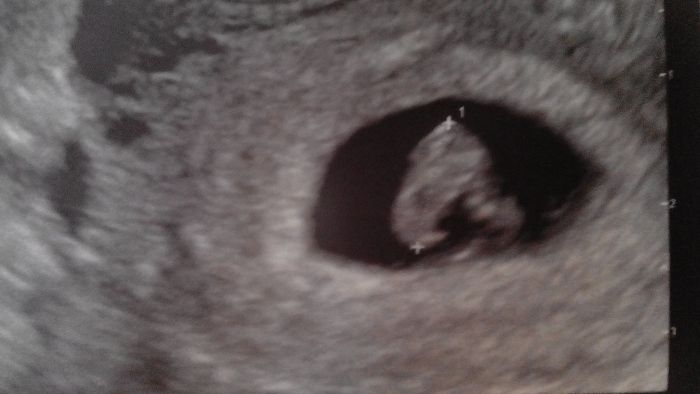

Já take hlasim ze kontrola dopadla dobre.Dle pm 7+2 dle velikosti 7+1 a mame 1 cm a srdicko.Jsem rada ze mini zanet dutin prezilo a zatim vse slape jak ma.Dostala jsem cipky na nevolnost s tim,ze kdyby se to nelepsilo,posle mi dr do nemocnice.Jinak do prace v tohle stavu pry nesmim :))))

Já dnes také koupila lízátka a dostala jsem ty čípky Torecan.Tak jsem zvedava zda to zabere :) Jo a dam vam sem fotku mimíse ;)